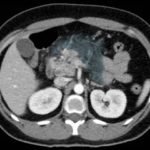

Computed tomography of the abdomen and pelvis with contrast show edema of the pancreas (red outline) and duodenum (yellow arrow) with peripancreatic inflammation, fluid and fat stranding (blue highlight). The distal pancreatic tail was noted to appear normal (green arrow). There was no organized drainable fluid collection, and no parenchymal hypo-enhancement. These findings are consistent with moderate severity acute interstitial pancreatitis.